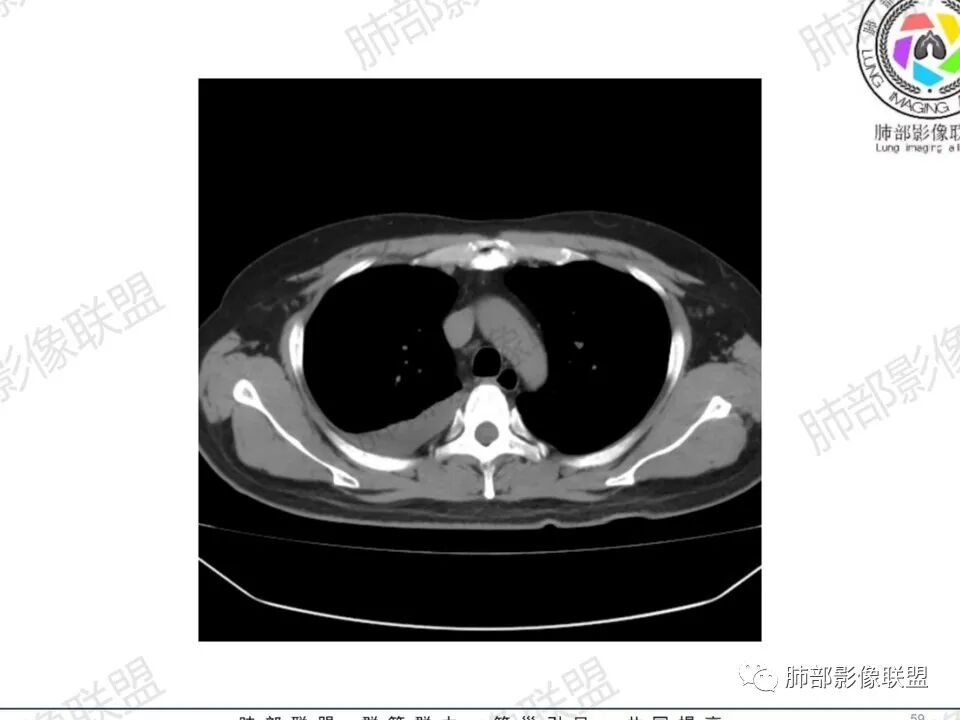

双肺多发结节,胸膜下为主,部分可见空洞。左肺上叶尖后段结节较大,分叶毛刺,周围可见长条索及小斑片影,内空洞比较光滑,内侧壁可见支气管通过。右肺下叶后基底段不张实变,后侧积液,右侧水平裂积液,右侧膈胸膜纵膈胸膜增厚积液,右侧侧胸膜肥厚,考虑1:一元金葡。2二元:金葡,左肺上叶结核。

中年男性,左手中指及胸壁疼痛伴发热来诊,影像见双肺多发结节,胸膜下分布为主,部分结节可见空洞,边缘模糊。左肺上叶尖后段结节较大。右肺下叶后基底段不张实变,右侧叶间裂及右侧胸腔积液,右侧侧胸膜肥厚。考虑金葡菌感染,血播SPE。